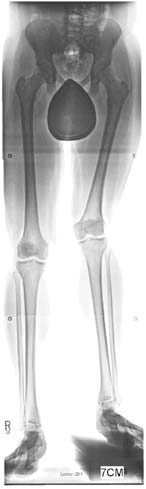

帕利等人(2013年)进行了一项回顾性单中心研究,基于某单一中心三位外科医生的经验[19]报告PRECICE系统的早期结果。本研究已获得机构审查委员会批准。结果首次于2013年4月在希腊雅典举行的欧洲小儿骨科学会年会上发表,随后在加拿大多伦多的北美小儿骨科学会(POSNA)上发表。该研究最近已发表[20]。作者回顾了2011年12月1日至2012年12月4日期间植入的48例连续患者(65个PRECICE钉)的结果(均为PRECICE 1)。本系列患者的平均年龄为25.6岁(10.3–58.4岁)。23名患者因先天性不等长(FIGURE 5)进行了延长;平均年龄为18.5岁(10.3–43.7岁),术前平均延长目标为4.91厘米(1.5–6.5厘米),而术前平均下肢长度差异为6.27厘米(1.5–18.2厘米)。延长速率为0.8毫米/天。除五名患者外,该组所有患者均达到了延长目标;平均延长长度为4.5厘米(0.5–6.5厘米)(FIGURES 6& 7)。四名患者因发育性不等长进行了延长;平均年龄为17.8岁(13–27岁),术前平均延长目标为3.68厘米(1.5–6.5厘米)。延长速率为1毫米/天。平均延长长度为3.68厘米(1.5–6.5厘米)。所有患者均无并发症地实现了术前延长目标。六名患者因创伤后肢体长度差异(FIGURE 8)进行了延长;术前平均目标为3.48厘米(1.7–5.0厘米),平均年龄为

术前前后位和侧位X光片。她既往曾接受超级髋‐超级膝手术,并在4岁时成功接受过一次外固定器延长术。她的腿部长度差异为7厘米。(B) 使用PRECICE 2 8.5毫米 245毫米、转子入路股骨钉进行5厘米延长后的前后位X光片。同时使用半骨骺阻滞板治疗其膝外翻。(C) 此为牵张停止一个月后愈合期的前后位X光片,显示牵开间隙正在由骨组织填充。)